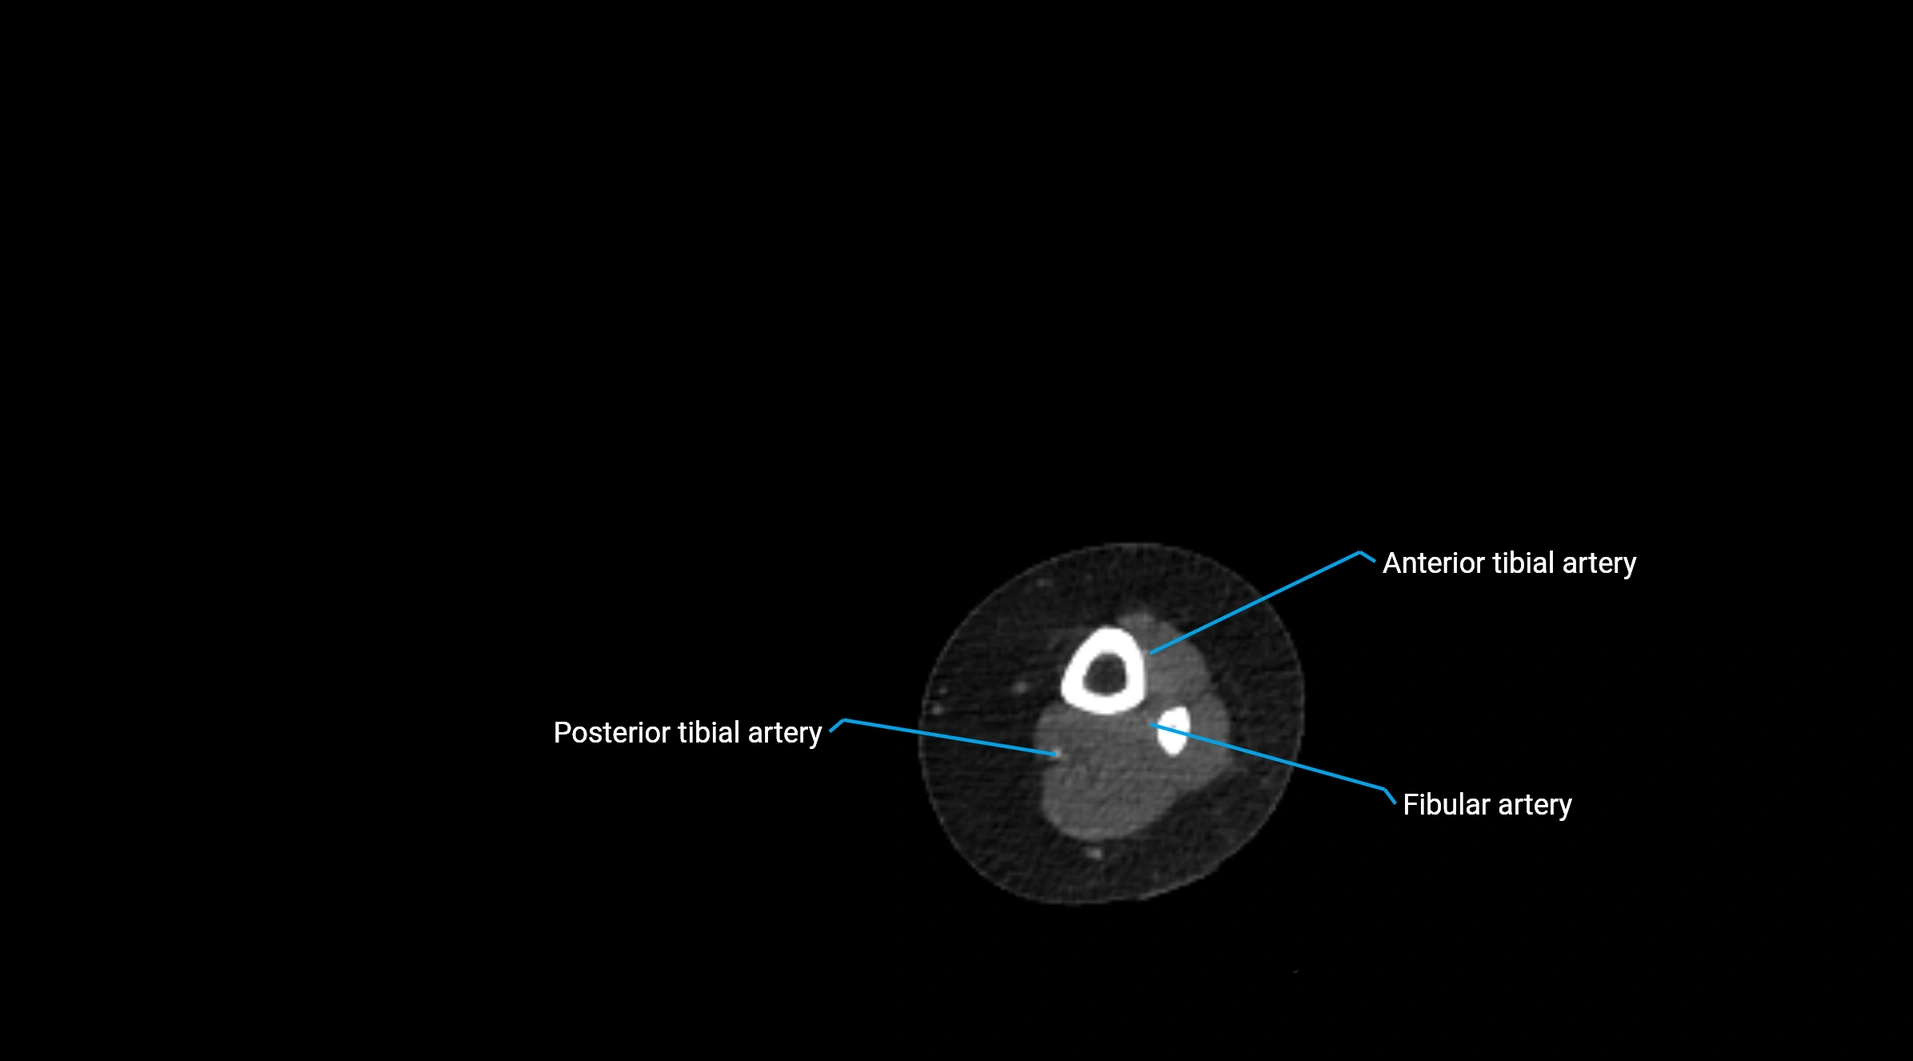

CT images

image